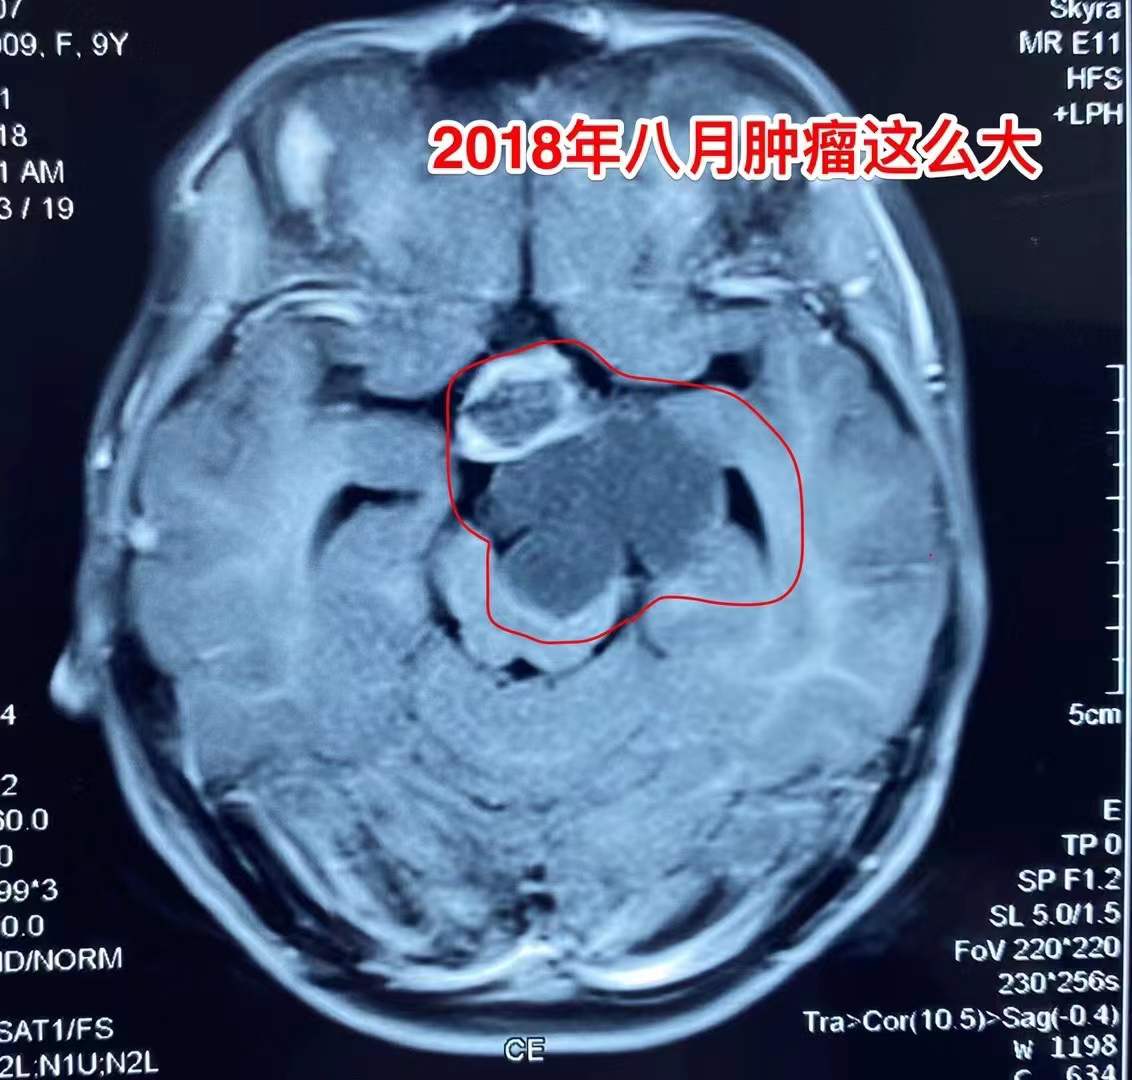

吃三年中药,颅咽管瘤能控制住吗?

12岁的女孩子,三年前因右侧偏身发麻,发现了脑部肿瘤,见图1、图2。家长害怕做开颅手术,就选择吃中药治疗。

图一

图二

到2022年一月患儿行走都有困难了,复查磁共振见图5、图6。肿瘤进一步长大了。从图8可以看出肿瘤有钙化,是典型的造釉细胞型颅咽管瘤。

对于颅咽管瘤,最有效的治疗是做手术切除肿瘤。中药治疗效果不确切,吃了三年中药,肿瘤体积增加了好几倍,即使再考虑做手术,其风险肯定也增加了不少。